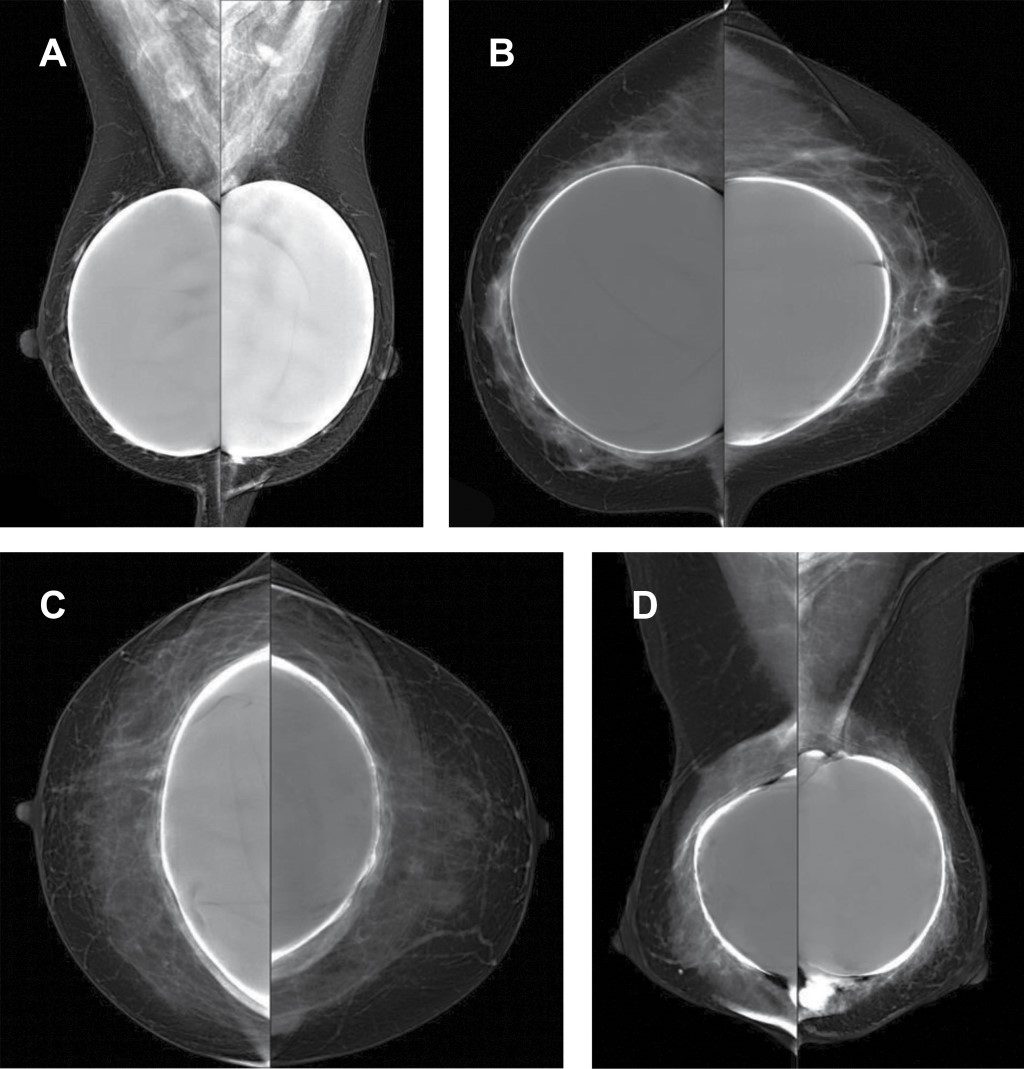

Evaluation by mammography and ultrasound of breast implants and their complications

Introduction: due to the increase in breast surgeries for aesthetic purposes and device development, radiological evaluation of breast implants constitutes an important part of daily activity for an imaging specialist. Objectives: describe the radiological findings of breast implants, pathologies, and cartographic assessment of the fibrous capsule, creating a scale that defines the main findings. Material and methods: a retrospective study was carried out to evaluate patients with aesthetic breast implants who underwent bilateral mammography and breast ultrasound, studying the age, placement, most common pathology, and mammographic description of the fibrous capsule by grade. Results: a total of 140 patients with an average age of 51.16 years were analyzed; the plane of placement of the prosthesis was sub glandular in 64.3%. The primary pathology associated with the implants was intracapsular rupture in 5.7% of the total sample, which had an average placement time of 14.7 years. The main finding in the fibrous capsule was capsular thickening. Conclusion: the evaluation of breast implants should be carried out with conventional diagnostic methods, and the prevalence of pathology is low. The fibrous capsule's evolution degrees can be assessed by mammography and associated with the average implant placement time.

Figure 1

Figure 2

Figure 3